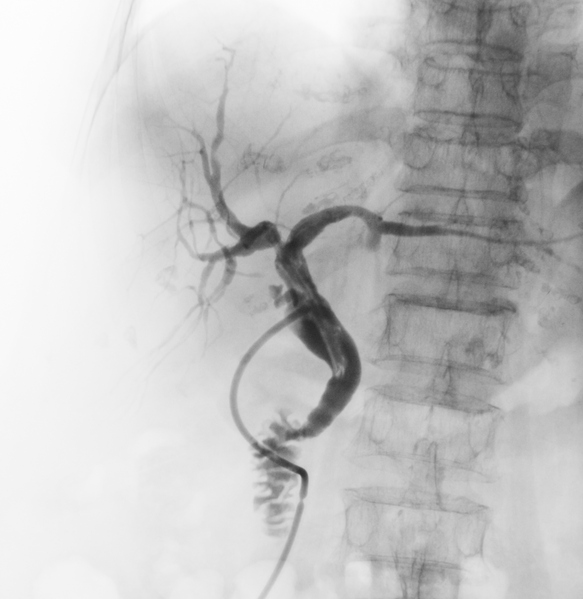

[caption id="attachment_391927" align="alignleft" width="292"]Computed tomography angiography (CTA) of abdominal aorta, oblique view [사진=게티이미지뱅크][/caption][한의신문=김대영 기자] 컴퓨터단층촬영(CT) 등 X-선 진단‧검사 시 사용한 조영제로 이상반응을 경험했다면 또다시 과민반응이 일어날 가능성이 68배나 높아지고 이상반응을 보인 가족력이 있다면 과민반응이 발생할 가능성이 14배 높은 것으로 나타났다.